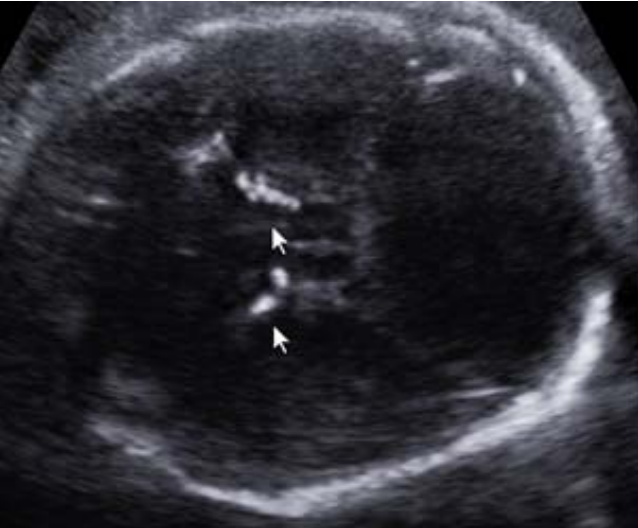

Paciente na 28ª semana, multípara, seis partos vaginais e sem pré-natal adequado vem à emergência obstétrica preocupada para mostrar uma ultrassonografia, a qual descreve uma circunferência cefálica abaixo de três desviospadrões para a idade gestacional e imagem abaixo:

Foi encaminhada para um serviço especializado, onde foi submetida à investigação diagnóstica. Na 39ª semana de gravidez, evoluiu com o parto vaginal. Ao nascimento, as alterações ultrassonográficas foram confirmadas, acrescidas de coriorretinite e atraso no desenvolvimento neurológio.

Baseado nesses sinais e sintomas, assinale a alternativa que sugere a principal hipótese etiológica fetal.